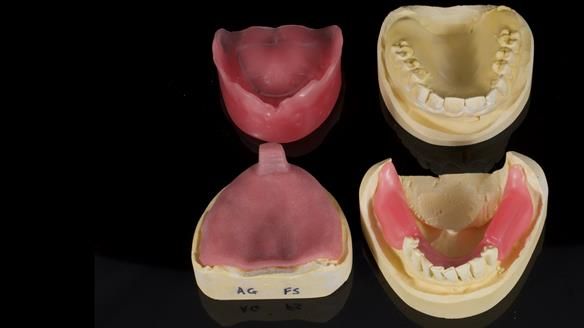

We provided her with an immediate upper denture (Mk 1), followed by a definitive metal-based upper denture (Mk 2). A lower removable partial denture was discussed, to be made only if needed once the upper treatment was complete. However, at review, this wasn’t necessary — Adnana had excellent neuromuscular control and function, even with a shortened dental arch (SDA).

Rowan, Sam Hesketh and Chris Hesketh provided the stunning technical work. I am very lucky to have them.

- Immediate denture (Mk 1) fitted the same day the teeth came out

- Definitive denture (Mk 2), metal-based and custom-designed for her face

- A restored smile, restored lip support, and a patient who owned the journey